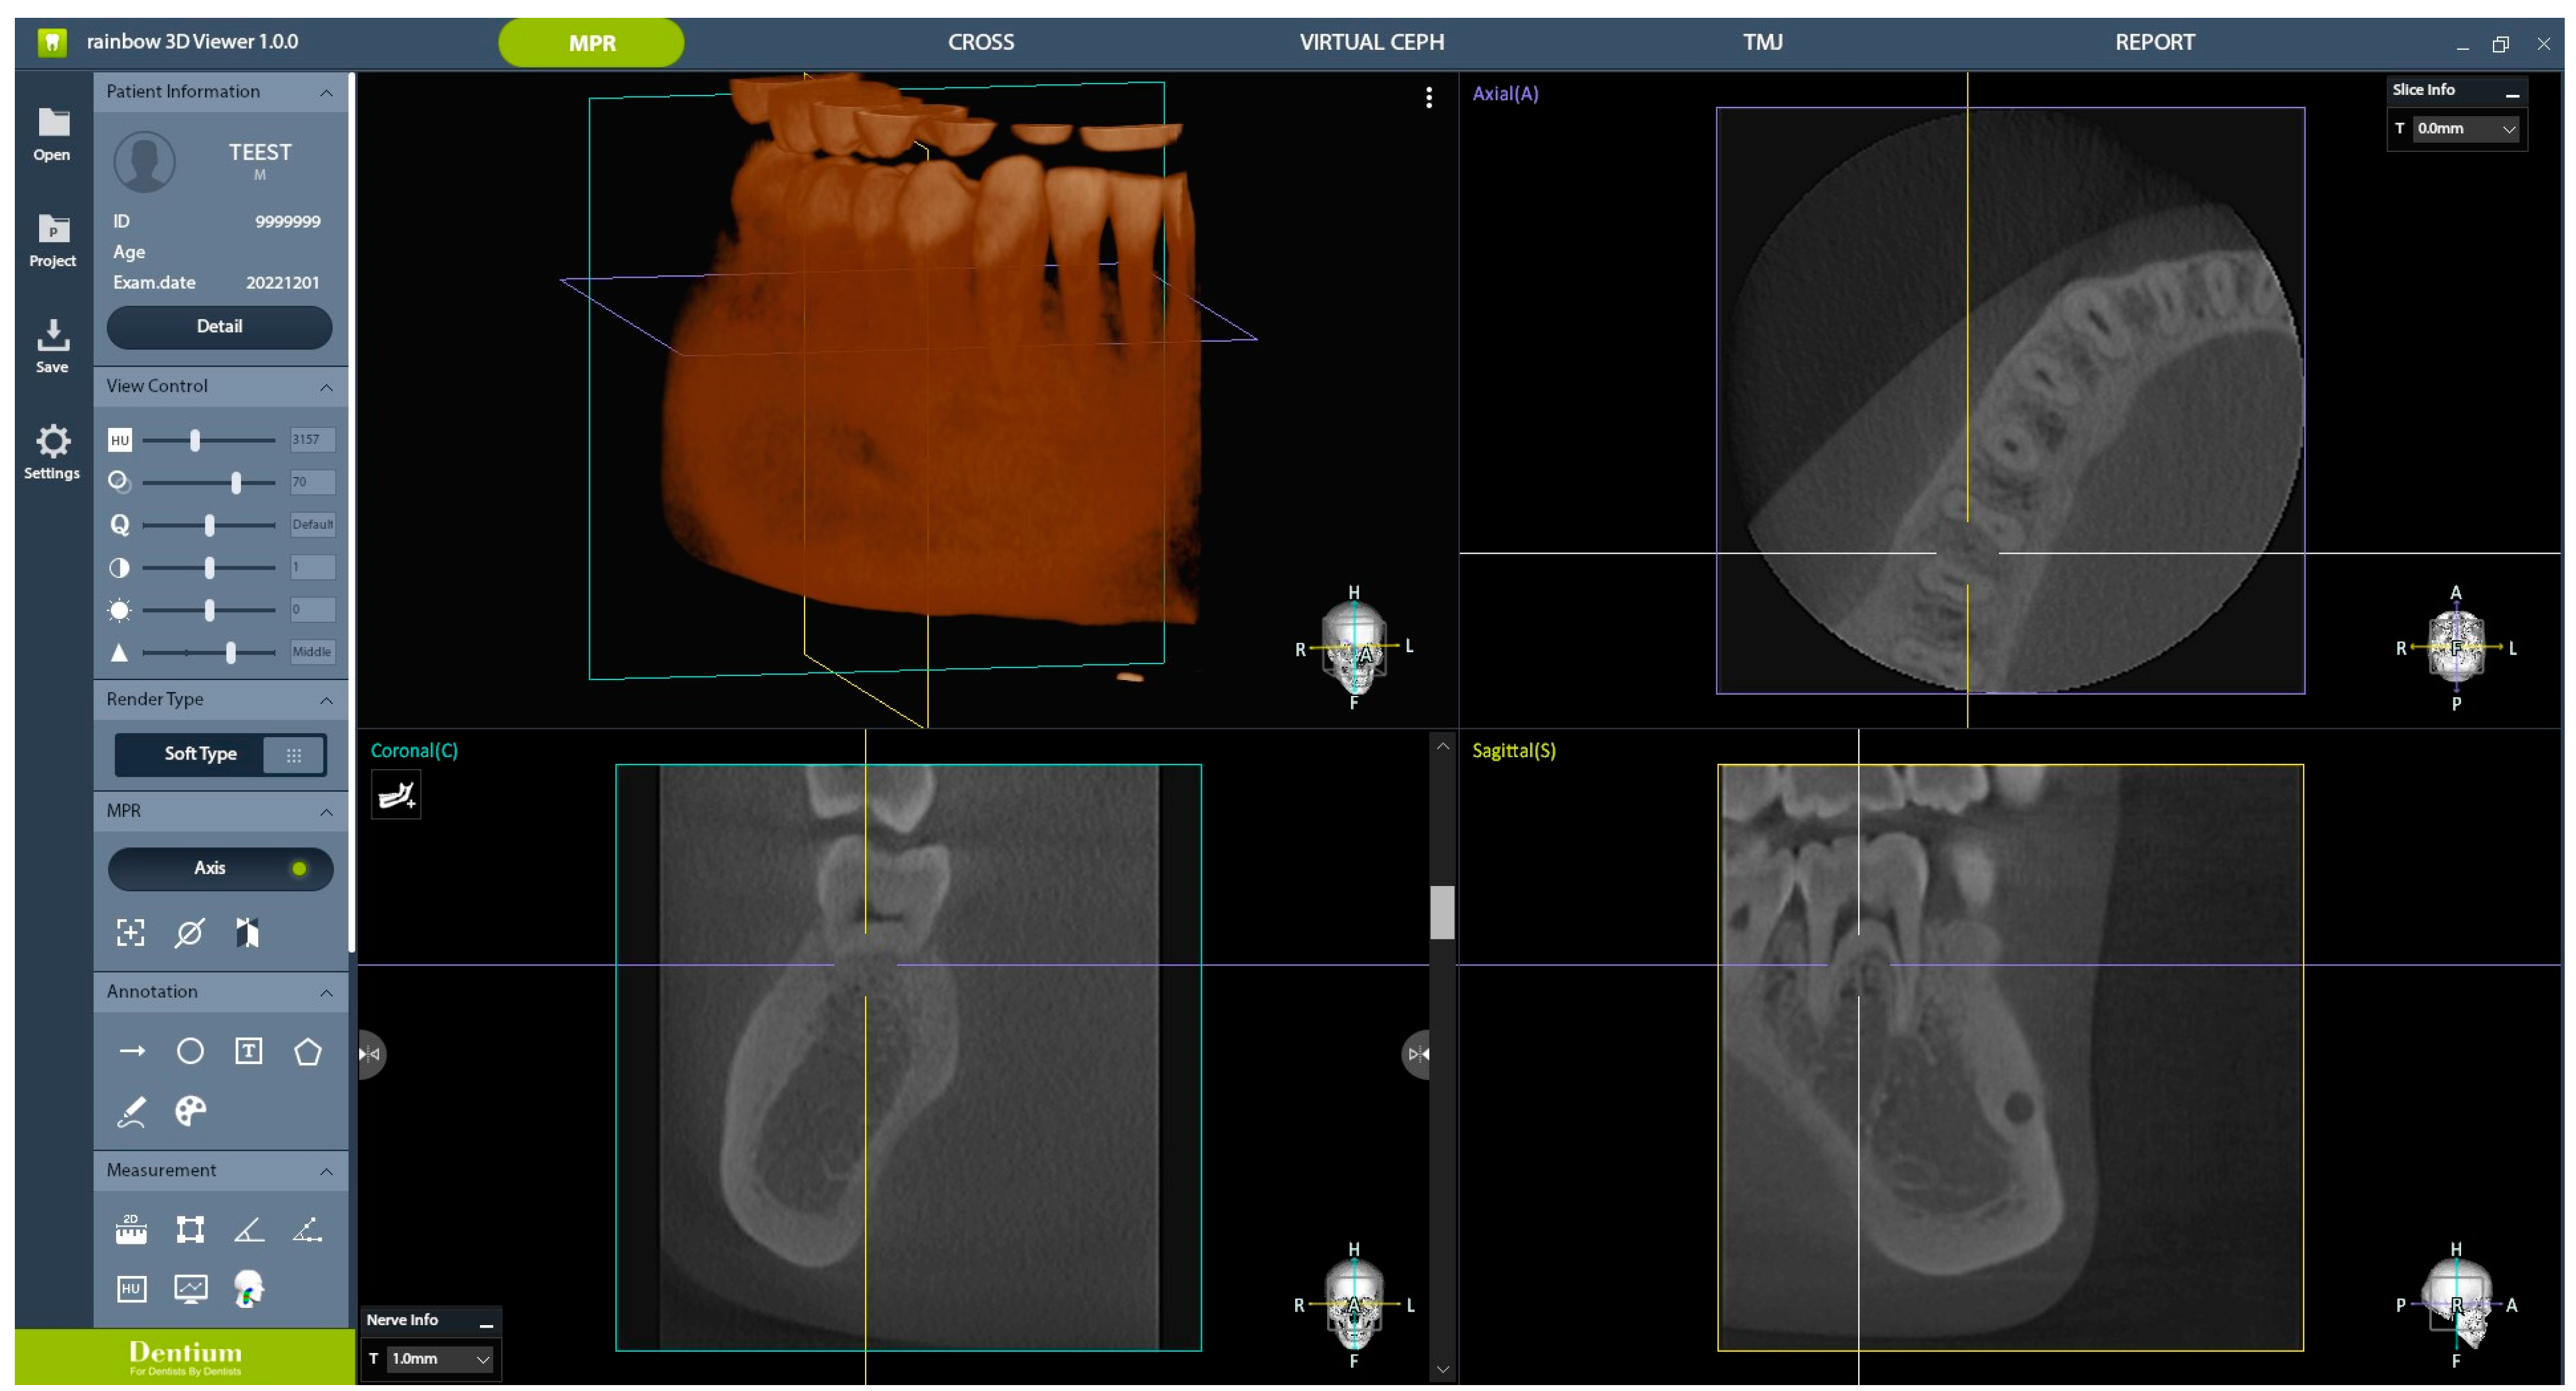

2. Materials and Methods

2.1. CBCT Scanning Protocol

2.3. AI Processing

2.4. Subjective Clinical Image Quality Evaluation